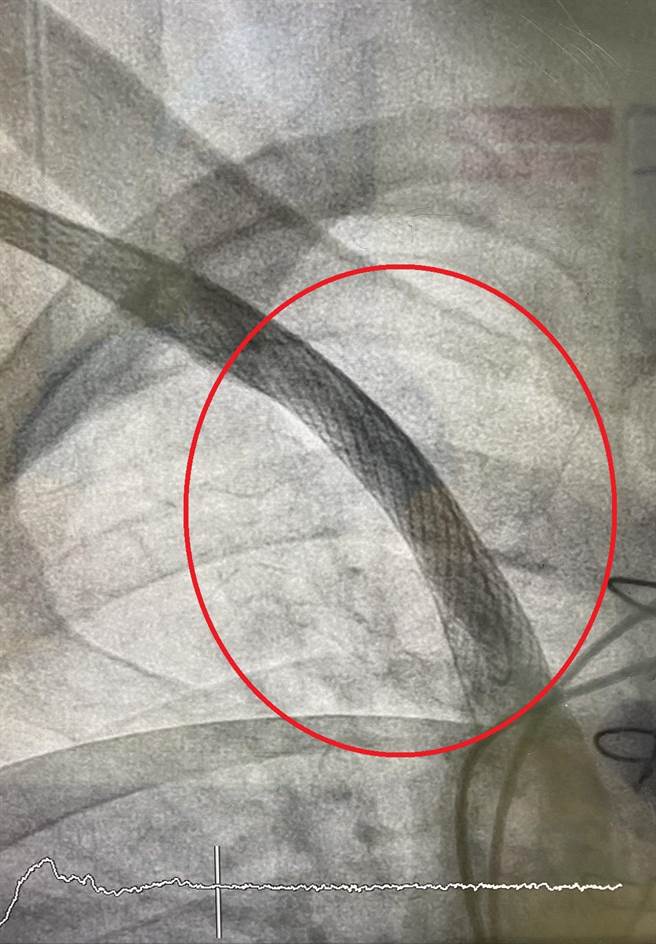

黄爷爷中心静脉血管狭窄(红圈处),每次洗肾时手臂会疼痛,无法顺利完成治疗。(大千医院提供/谢明俊苗栗传真)

80岁的黄爷爷是长期洗肾病人,2年前开始觉得洗肾时手臂会疼痛,医师安排血管摄影检查,发现他的中心静脉血管狭窄,经医师为他安排中心静脉支架手术,顺利解决黄爷爷血管狭窄的情形,让他不需再烦恼洗肾时疼痛的问题了!

大千综合医院心臟外科主任杨智钧表示,血液透析的洗肾病人手臂上会装设洗肾瘻管,洗肾过程中常因流速不足、压力过高、阻塞等问题,造成手痛、甚至痛到肩膀和脖子的情形,严重影响治疗,此时就要考虑是否为「中心静脉狭窄」的问题。

医师解释,所谓的中心静脉是指靠近心臟附近的大静脉,如同小水沟的水流到大河流再到大海一样,手上洗肾瘻管的血液会匯流到肩膀跟锁骨附近的大静脉,最后再流入心臟。由于静脉原本的压力很低,做洗肾瘻管之后,受到长期高速血流的衝击,就容易产生中心静脉狭窄的现象。根据资料统计,约有30%的洗肾病人会面临此种问题,但第一时间不需马上做处理,只有洗肾时出现手疼痛或肿胀才需治疗。